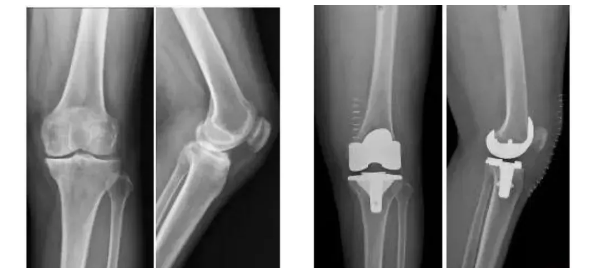

膝關節骨關節炎是一種退行性疾病,近年隨著經濟發展和人口老齡化趨勢日趨明顯,尤其是在中老年群體發病率較高,因此膝關節置換術需求量日益增長。此外,隨著居民生活水平的提高,大多患者對于膝關節置換術術后的生活質量和植入假體有了更高的要求,隨之假體在設計和創新方面也更精準、更便捷化。全球shou款3D打印分區骨小梁生物型膝關節假體正是在這種高需求與高期待的新形勢下應運而生。

目前臨床上使用的膝關節假體多為骨水泥固定型假體,骨水泥即骨粘固劑,它可以將膝關節假體固定在骨界面上。骨水泥固定存在一定局限,如骨水泥單體具有一定的毒性;與骨接觸面的骨溶解問題;隨著時間推移,會發生變形和退變等。

本次植入的生物型膝關節假體在術中無需使用骨水泥,通過機械方式進行固定,即假體與骨組織的緊密結合,獲得假體的初始穩定性,遠期骨組織長入假體表面的微孔內部,實現由機械固定向生物.內鎖固定的轉化,zui終經過骨整合作用獲得良好固定,預期能夠獲得更長的假體壽命。此外,生物型膝關節假體避兔了骨水泥相關并發癥的發生,縮短了手術時間,zui大程度保留了骨組織。因而減輕了患者術后疼痛,降低了圍術期并發癥發生率,有利于患者術后快速康復。

周宗科教授介紹說,該款3D打印分區骨小梁生物型膝關節假體有三個亮點,一是脛骨平臺假體采用了3D打印骨小梁分區技術,三分區設計使宿主骨均勻骨長入,避免因應力分布不均而造成平臺假體松動等問題;二是所用股骨髁假體表面為真空等離子噴涂純鈦涂層,其粗糙的接觸面增加了骨誘導的能力,具有優異的即刻穩定和長期穩定性;三是所用平臺墊為添加維生素E的高交聯超高分子量聚乙烯材質,具有優異的耐磨性能。